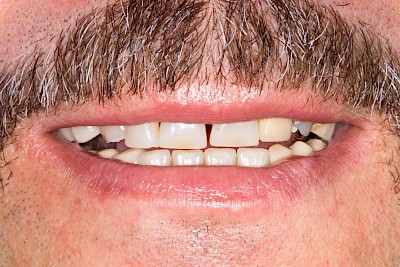

Provisorische Prothese

Manchmal müssen mehrere Zähne auf einmal gezogen werden. Bis die Wundheilung abgeschlossen ist und richtige Zahnprothesen hergestellt werden können, muss nicht selten eine gewisse Zeit (3-6 Monate) abgewartet werden. In dieser Zeit bekommen Patienten sogenannte provisorische Prothesen, wenn dies von den Patienten gewünscht ist. Diese kostengünstigen "Interims-Prothesen" bestehen meist nur aus Kunststoff und halten in vielen Fällen mit einfachen Klammern, die aus Draht gebogen sind. Manchmal wird auf die Klammer auch verzichtet. In seltenen Fallen kann es auch vorkommen, dass die Klammern ebenfalls aus besonderem Kunststoff bestehen.

Manchmal wird bei einer notwendigen Erweiterung einer Zahnprothese – wenn beispielsweise ein weiterer Zahn im Laufe der Zeit gezogen werden muss – auch einfach eine Klammer aus Draht gebogen und eingearbeitet. Es kommt auch vor, dass nie eine neue, endgültige Zahnprothese gefertigt wurde und die Interims-Prothese die einzige Versorgung ist und bleibt.

Ganz selten wünschen sich Patienten eine Lösung ohne "Kunststoff-Platte". Vor allem wenn im Fronzahnbereich Zähne fehlen kann dann ein weiter Lösung sein, mit einer Tiefziehschiene über die Zähne die Lücken zu schließen, in dem die Schiene im Bereich der fehlenden Zähne mit zahnfarbenem Kunststoff "ausgegossen" wird.

Provisorische Prothesen können aufgrund der einfachen Konstruktion leichter brechen.

Beispiele 24 Bilder